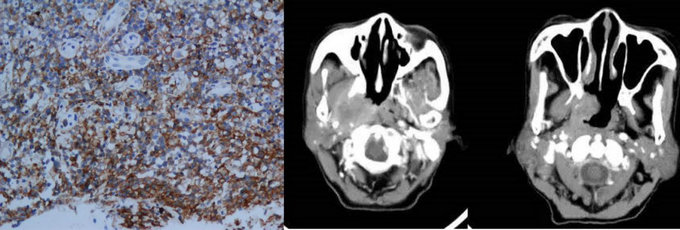

½áÍâ±ÇÐÍNK/Tϸ°ûÁܰÍÁö£¨¼ò³ÆNK/TÁܰÍÁö£©ÊÇÎÒ¹úµÚ¶þ³£¼ûµÄ·Ç»ôÆæ½ðÁܰÍÁöÑÇÐÍ£¬£¬ÔÚÎ÷Å·¹ú¼ÒÓÐÊý£¬£¬ÌØ·¢ÓÚÖйúµÈÑÇÖÞ¹ú¼Ò¡£¸Ã²¡¹Å°åÖÎÁÆÐ§¹ûÇ·¼Ñ£¬£¬Ô¤ºó²»¼Ñ¡£½áÍâ±ÇÐÍNK/Tϸ°ûÁܰÍÁöûÓÐ×ÔÁ¦·ÖÆÚϵͳ£¬£¬ºã¾Ã½èÓûôÆæ½ðÁܰÍÁöAnn Arbor·ÖÆÚ¡£

NK/TÁܰÍÁö²¡Àí¼°Ó°ÏñÌåÏÖ

¾ÝÁÖÍ©ÓܽÌÊÚ½éÉÜ£¬£¬CA·ÖÆÚÄÉÈëÁËÆù½ñΪֹ×î´óÑù±¾Á¿µÄ½áÍâ±ÇÐÍNK/Tϸ°ûÁܰÍÁö²¡ÀýÊý£¬£¬¹²ÓÐ30¼ÒÖ×ÁöÖÐÐĵÄ2153¸ö²¡ÀýÄÉÈëÑо¿£¬£¬ÊÇÏÖÔÚÌìÏÂÉÏ×î´óµÄNK/TÁܰÍÁöÊý¾Ý¿â¡£Ñо¿·¢Ã÷ÏàÁÚ¹ÇÖÊ¡¢¡¢¡¢Æ¤·ôºÍ±ÇÅÔñ¼ÇÖÕ¼¡¢¡¢¡¢·Ç±ÇÐͲ¡±ä»òÀÛ¼°¾Ö²¿ÁÜͶºÏµÈΪ ½áÍâ±ÇÐÍNK/Tϸ°ûÁܰÍÁöµÄ×ÔÁ¦¸ßΣÒòËØ¡£¾Ý´Ë£¬£¬Ñо¿ÍŶӹ¹½¨ÁËCA·ÖÆÚ£º£º£º